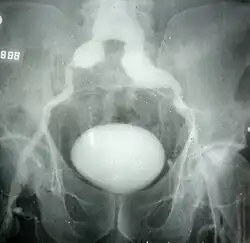

Tętniak prawdziwy (łac. aneurysma verum; ang. true aneurysm) – workowate poszerzenie światła naczynia, przy zachowaniu ciągłości ścian o pierwotnej budowie. Związany z wrodzonym defektem budowy ściany tętnicy (np. zespół Marfana) lub powstały na skutek jej osłabienia przez proces zapalny. Może być skutkiem urazu. Występuje w większości tętnic. Leczenie polega zazwyczaj na wycięciu i wstawieniu protezy naczyniowej. W przypadku naczyń mózgowych leczenie polega, jeżeli to możliwe, na zaklipsowaniu tętniaka. W innych mniejszych naczyniach pozostawia się je bez leczenia. Tętniaki prawdziwe aorty o średnicy poniżej 4 cm nie podlegają leczeniu. Tętniaki większe leczone są tylko w przypadkach zagrażających pęknięciem (np. szybko poszerzający się tętniak).